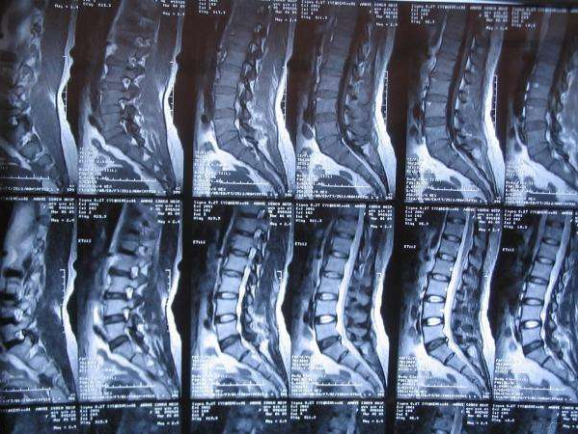

腰椎核磁共振显示巨大突出压迫神经

图片尺寸1280x950

术前磁共振椎间盘明显突出压迫脊髓神经

图片尺寸2000x2666